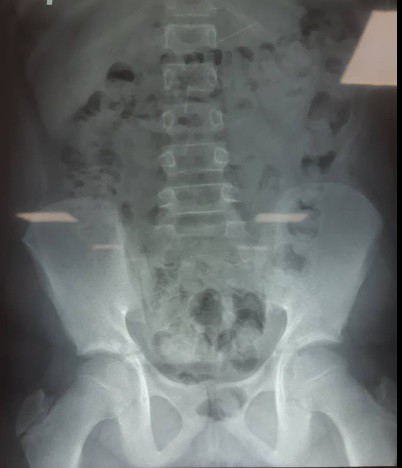

Hình ảnh chụp Xquang của bệnh nhi.